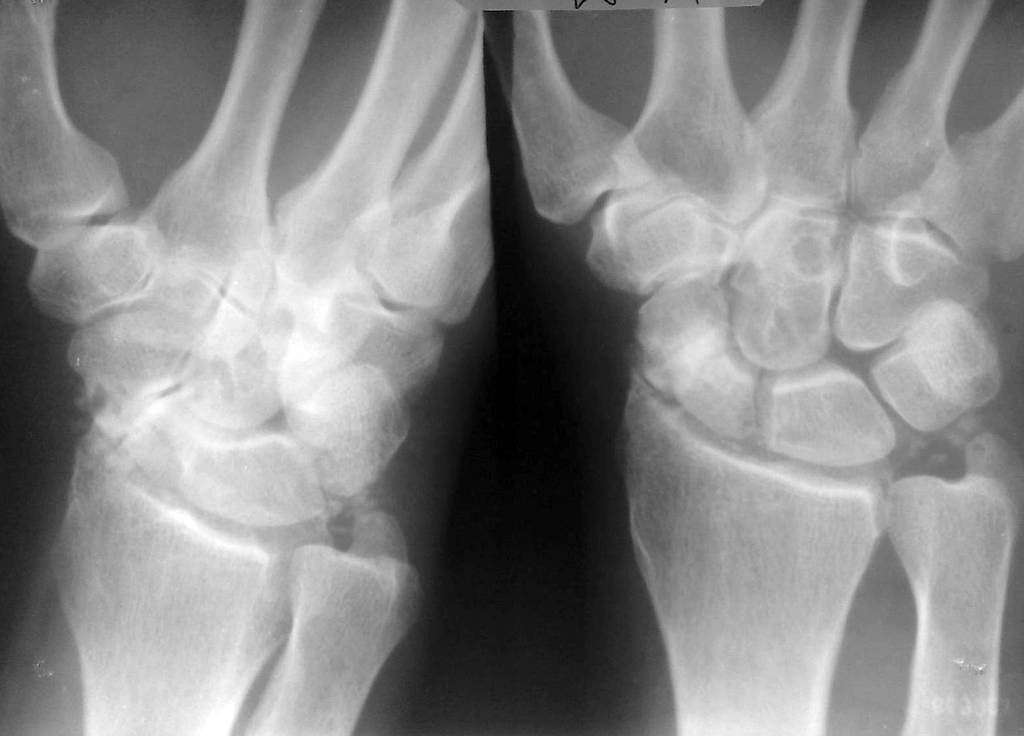

Перелом ладьевидной без смещения 84 фото